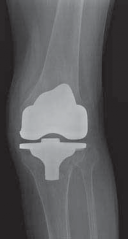

Revision Arthroplasty with Tibial Bone Loss: Bone Grafting Solutions

Illustration of arthroplasty with tibial bone - Dr. Mohammed Hutaif

Looking for accurate information on Revision Arthroplasty with Tibial Bone Loss: Bone Grafting Solutions? Tibial bone loss is a complex issue in revision knee arthroplasty, presenting as significant bone defects that challenge implant stability. Successful management of **arthroplasty with tibial bone** loss utilizes methods like cement fill, metal augments, or bone grafting to restore anatomical support. Smaller defects are addressed with morselized graft, while larger ones may necessitate metallic wedges or structural allografts.

Substantial bone loss and complex osseous defects represent some of the most formidable challenges encountered by orthopedic surgeons performing revision total knee arthroplasty (TKA). As the volume of primary TKA procedures continues to rise globally, the corresponding burden of revision arthroplasty has increased proportionally. Tibial bone loss in the setting of a failed TKA is a particularly complex problem, demanding meticulous preoperative planning, advanced reconstructive techniques, and a thorough understanding of implant biomechanics.

Awareness and proper management of metaphyseal and diaphyseal bone loss are crucial for achieving immediate mechanical stability and ensuring the long-term longevity of the newly implanted revision components. While modern highly porous metallic augments, cones, and sleeves have gained popularity, bone grafting—both morselized and structural—remains a fundamental biologic solution, particularly for restoring bone stock in younger patients or those with catastrophic osseous deficiency.